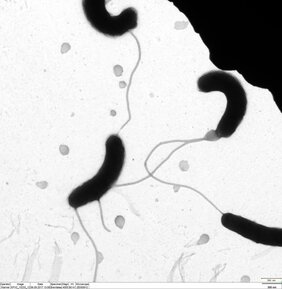

Das Protein CrvA kommt im periplasmatischen Raum des Bakteriums vor. Dieser liegt zwischen der äußeren Zellwand und der ebenfalls von einer Membran umgebenen Grundsubstanz der Zelle, dem Cytoplasma. Dort bestimmt CrvA die Krümmung des stäbchenförmigen Bakteriums V. cholerae. „Bisher war nicht bekannt, wodurch das Protein reguliert wird. Wir konnten mit der kleinen Ribonukleinsäure VadR ein Molekül identifizieren, das die Synthese dieses Proteins hemmt“, sagt Papenfort. Kleine Ribonukleinsäuren enthalten im Gegensatz zur Boten-RNA keine Erbinformationen, beeinflussen diese allerdings – meist nach der Überschreibung der DNA zur Boten-RNA.

„Cholera-Bakterien, bei denen das Protein CrvA nicht durch VadR unterdrückt wird, zeigen eine verminderte Überlebensrate bei Kontakt mit Penicillin“, so Papenfort. Das weise darauf hin, dass der Erhalt der Zellform durch VadR für die Antibiotikaresistenz entscheidend sei, fügt der Mikrobiologe hinzu. Die Forschenden deckten weitere Funktionen der kleinen RNA VadR auf, darunter auch auf die Bildung von Biofilmen, die eine wichtige Rolle bei der Pathogenität von V. cholerae spielen.